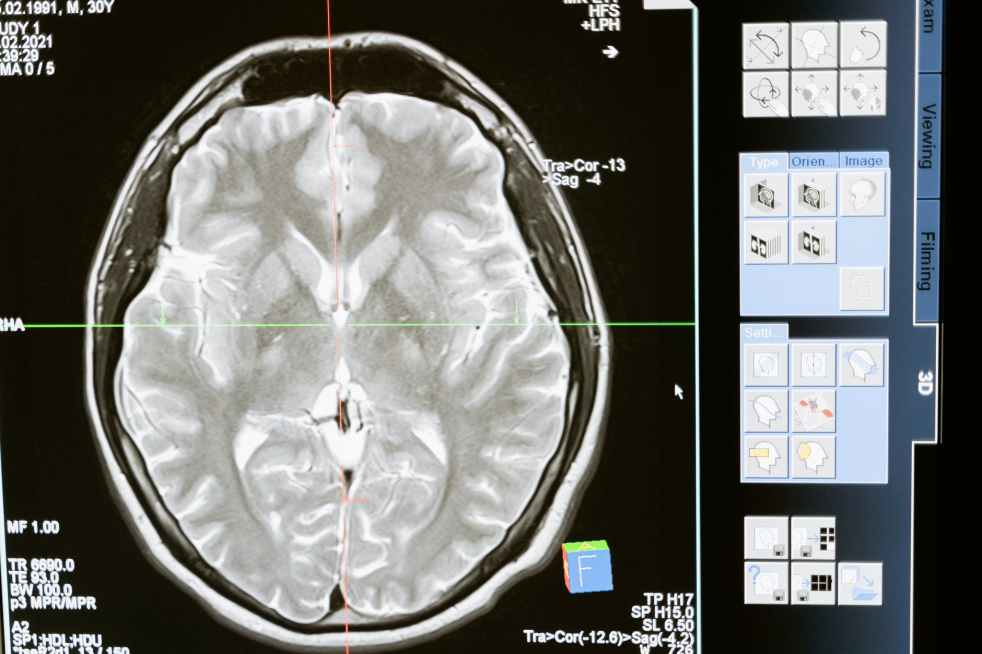

According to the Mayo Clinic, multiple sclerosis is a chronic autoimmune disease that causes a breakdown of the protective covering of nerves, causing numbness, weakness, trouble walking, vision changes and other symptoms.

MS causes an interruption in communication between the brain and the rest of the body, and can eventually lead to permanent damage of the nerve fibers.